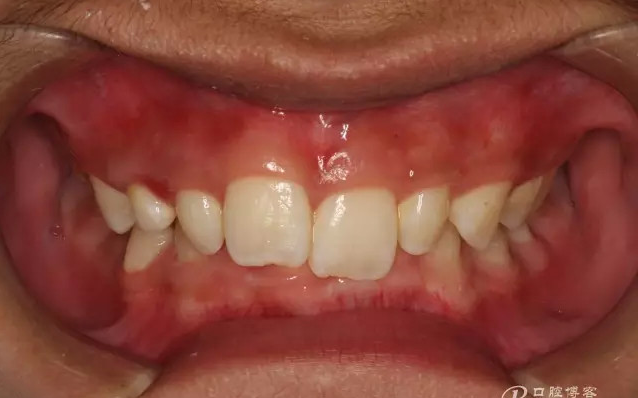

圖1.術(shù)前閉口位影像:深覆合。